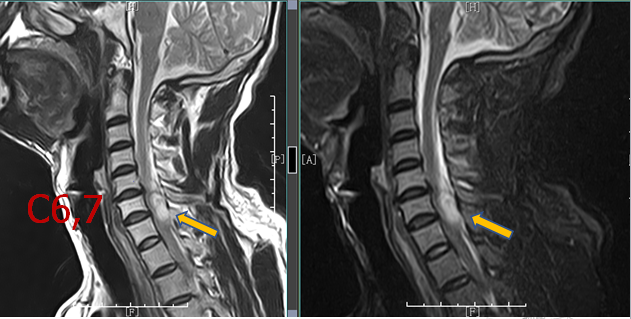

诊断:颈椎后纵韧带骨化、颈椎过伸伤、颈椎间盘突出